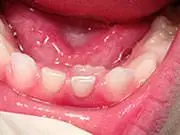

Baby Teeth - Pediatric Dentist Adult Teeth Coming in Behind Baby Teeth

This is a very common occurrence with children, usually the result of a lower, primary (baby) tooth not falling out when the permanent tooth is coming in. In most cases if the child starts wiggling the baby tooth, it will usually fall out on its own within two months. If it doesn't, then contact your pediatric dentist, where they can easily remove the tooth. The permanent tooth should then slide into the proper place.